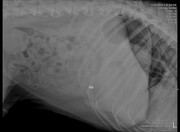

Добавлено (12.11.2018, 20:37) --------------------------------------------- Сил нет писать. Просто нет ни каких моральных сил. Нужно дойти до стадии принятия и жить дальше. Вот, что я узнала. при ортопедическом осмотре нарушений со стороны опорнодвигательного аппарата не выявлены. ( не считая старых травм, на кануне укол получил, поэтому не хромал). Рентген делали без миорелаксанта. Не хотела его "нагругжать". По ним вроде, тоже с суставами все ок. Есть подозрение на грыжу в отделе между последним кресцовым и первым хвостовым. Анализ мочи в норме, кроме кислой среды. На узи нашли наше старое новообразование. Оно немного меньше (на пол см.) . При ректальном осмотре простата совсем маленькая (около 1 см) (это потому что мы его кастрировали) Самое плохое, что на рентгене мы нашли еще одно новообразование. Оно давит и на мочевой и на кишечник и может быть причиной болей. С сегодняшнего дня у Цезаря подтекает моча. Если лежит на одном месте пару часов, лужа 20 см.образуется. Какал раньше 3 раза в день. Сейчас 1 раз. На сегодняшний день, колю мелбек и мильгамму. Аппетит хороший, бегает, по лестнице ходит. Если НПВС обезбаливает - это точно боль связанная с нервом, а не с новообразованием. Возможно он передавлен. Я пока не придумала, что делать???? Вообще..... Я точно знаю, что хочу как можно меньше страданий ему принести и переживаний. Он все эти клиники переносит с таким стрессом. Я хочу любить его и баловать. Но в то же время - я врач - и сидеть сложа руки не могу. Вот что я прошу! 1) может возможно снимки показать заочно Строку или еще кому-то в МИнске, послушать их! 2) если решать обезболивать, я за трококсил. Т.к. уезжаю и не смогу контролировать процесс. 3) дайте совет, кто сталкивался с подтеканием, с запорами из-за уменьшения просвета кишечника. Как вы справляетесь? Памперсы? Или что-то можно придумать? 4) Хочу услышать много мнений и все переварить. Но пока вот что я думаю. Цезарь мой родной человек. ТО есть лучше человека. И я не хочу последние его месяцы мучать , оставлять одного. Мне сейчас написали врачи - однозначно оперировать! Передавливает кишечник и может быть поздно.Но я не знаю.... я не хочу чтобы он умер на операционном столе или чтобы после операции было еще хуже. Я прошу совета!!!!!